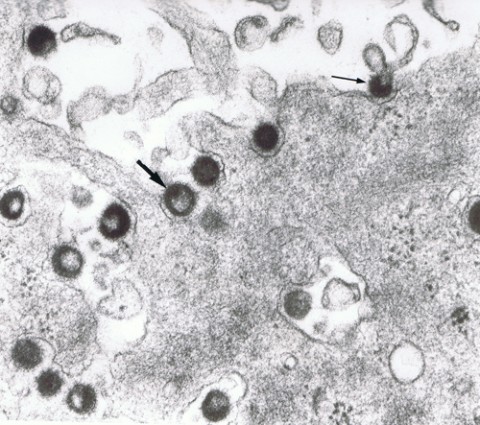

The HERV-W gene family, including the MS-associated retrovirus (MSRV) discovered more than 20 years ago, has been linked to MS prognosis and progression. (The HERV-K family is associated with amyotrophic lateral sclerosis.) Last year, the ENV antigen was reported in 75% of blood samples of people with MS but rarely among controls (Perron et al., 2012). Epstein-Barr virus and human herpesvirus 6 infections can turn on the sleeping retroviral genes. HERV-W may first be activated in circulating innate white blood cells called monocytes and macrophages. In MS, the cells travel to the brain, where they may spew viral particles that eventually infect the resident innate immune cells known as microglia. The viral particles may also aggravate the immune reaction indiscriminately. Other studies have shown that ENV has major pro-inflammatory and superantigenic immunological effects, Küry said.